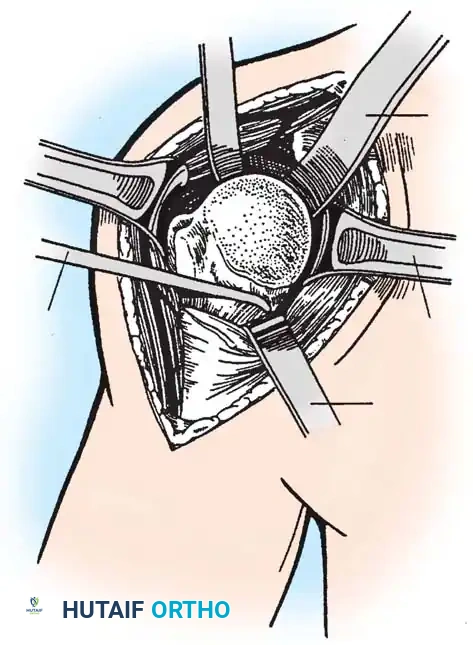

4. Glenoid Preparation

Excellent exposure is critical. Release the inferior capsule completely from the glenoid rim.

* Identify the center point of the glenoid.

* Perform concentric reaming to correct version and create a bleeding bone bed.

* Pitfall: Avoid excessive reaming, which penetrates the dense subchondral bone plate and enters the weaker cancellous vault, leading to catastrophic early subsidence.

Cement the all-polyethylene glenoid component using pulsatile lavage, meticulous drying, and pressurization techniques.